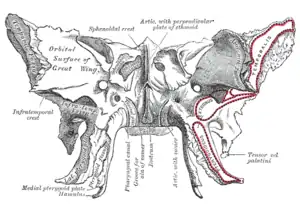

Sphenoid bone. Anterior and inferior surfaces.

Sphenoid bone. Anterior and inferior surfaces. Mandible. Inner surface. Side view.